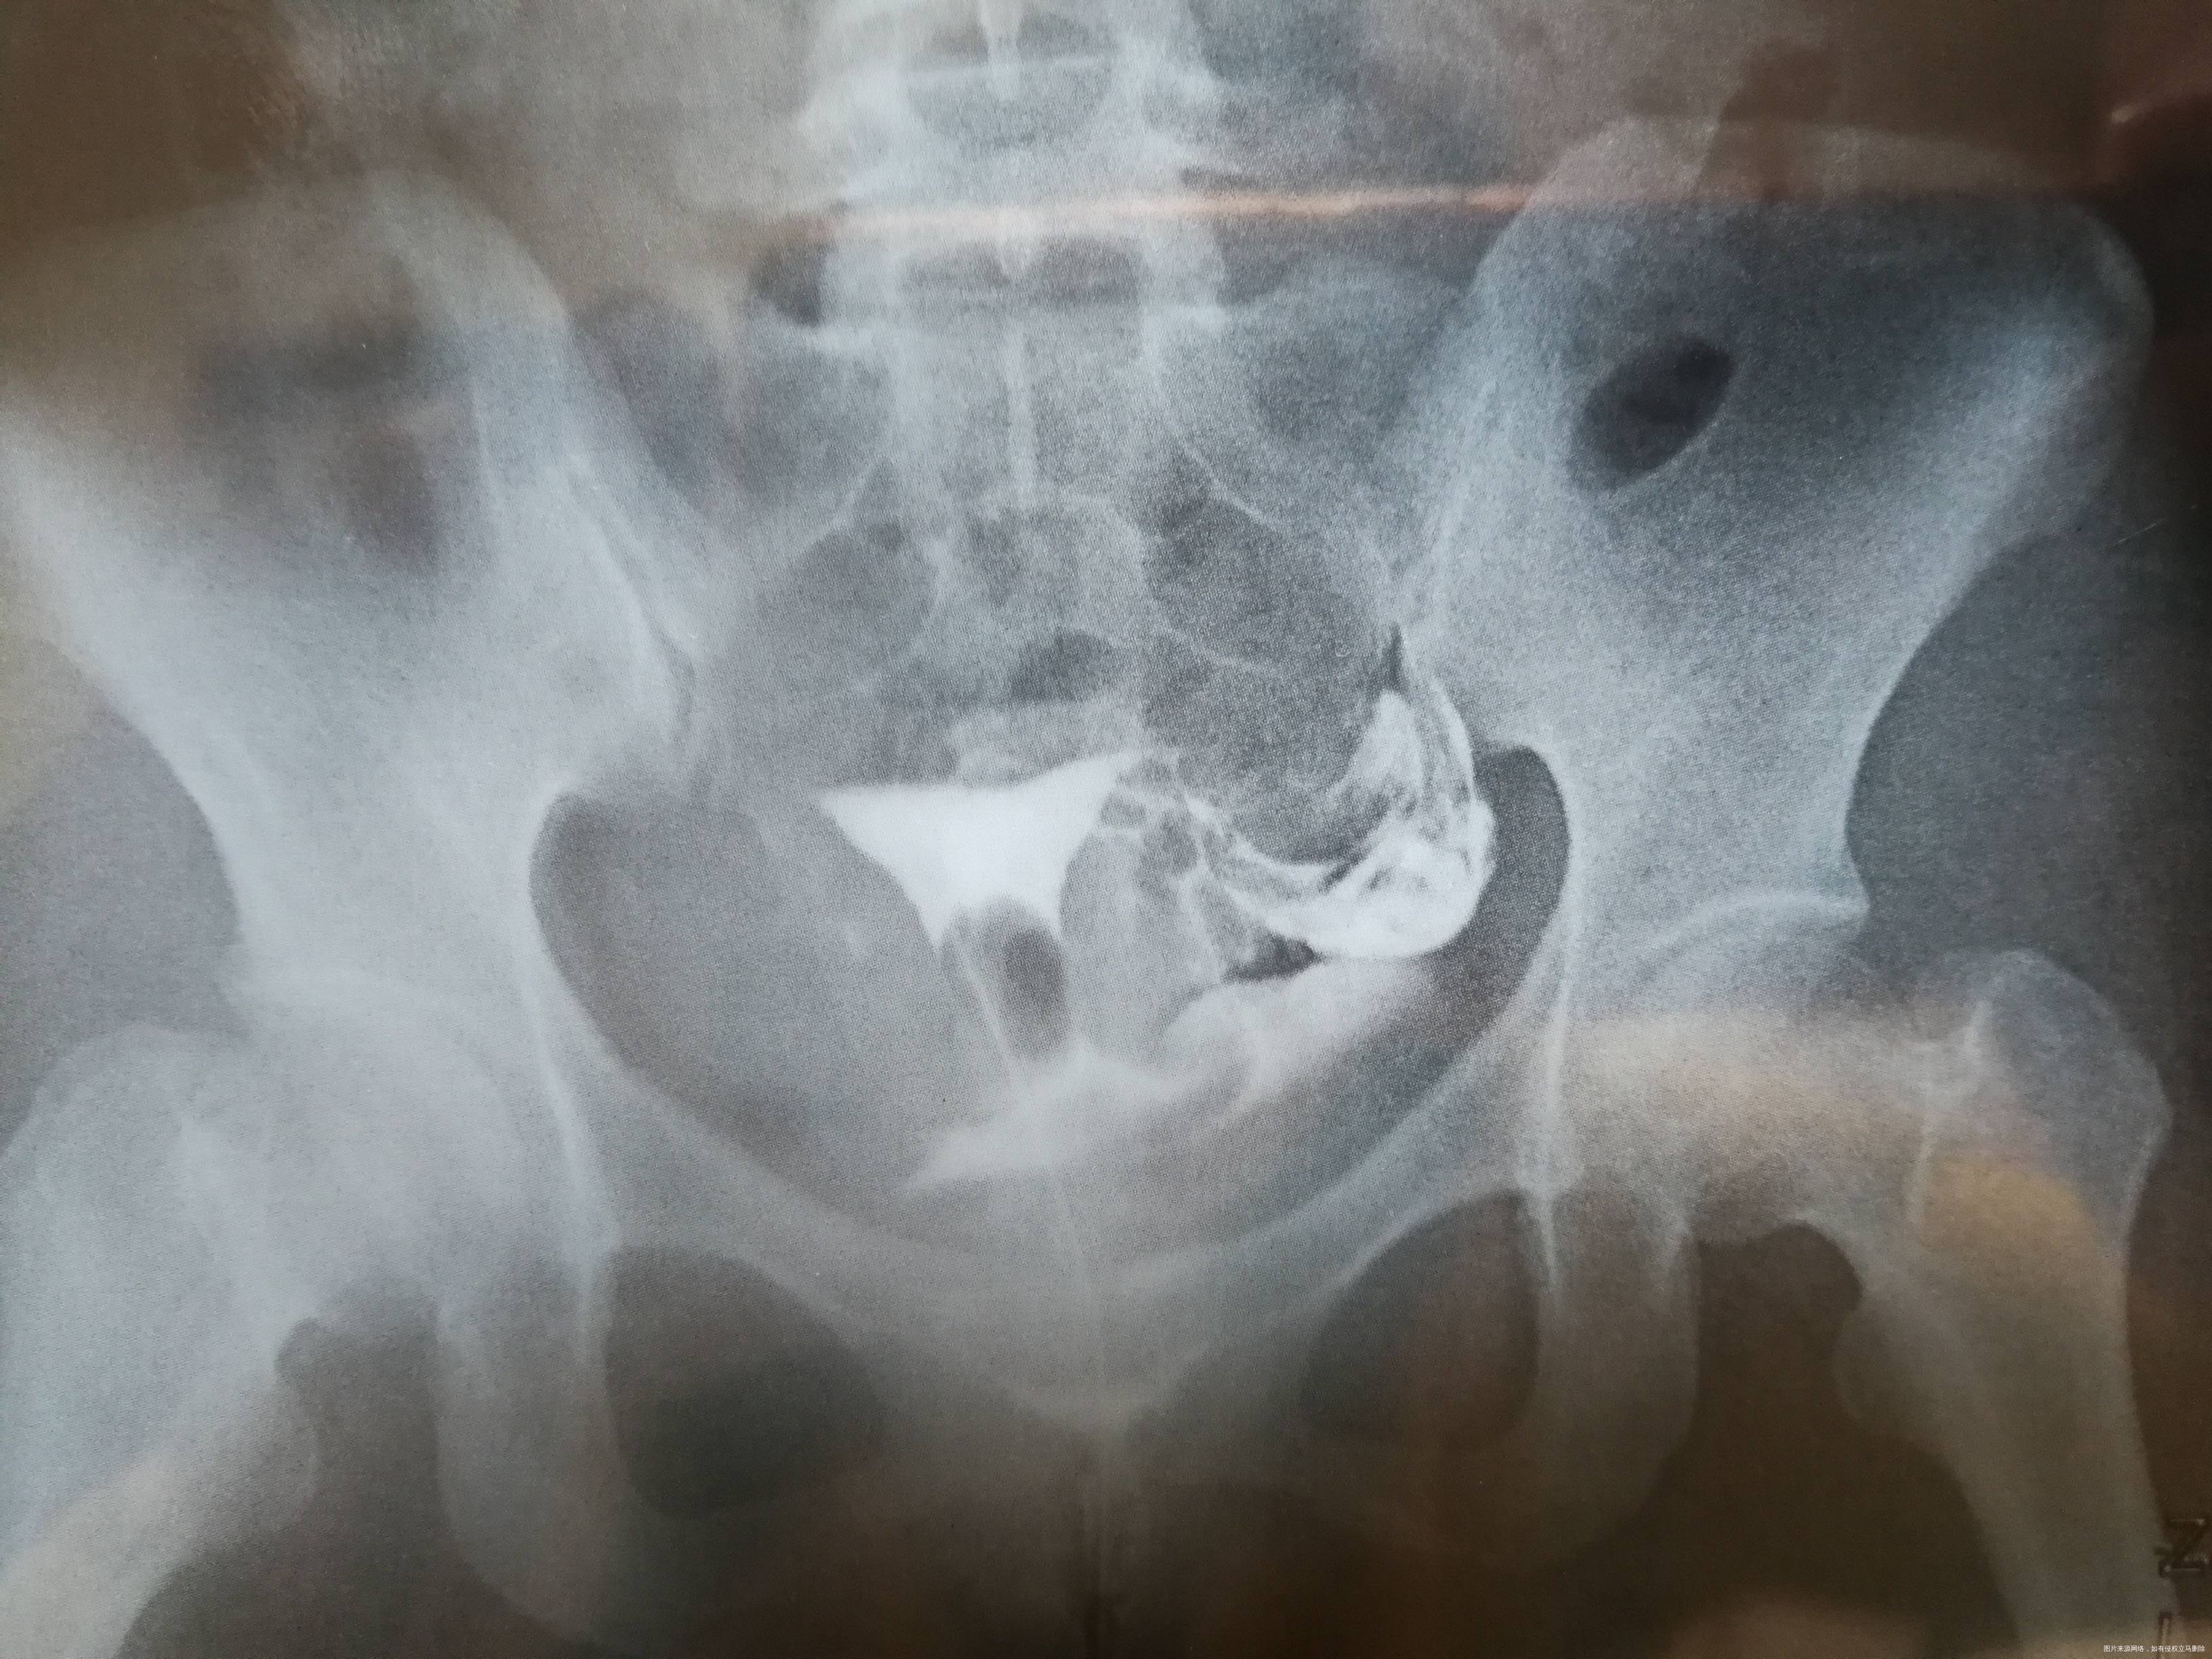

平片示盆腔区未见异常。电视下从双腔气囊管内注入30%碘普罗胺3ml、6ml分别点片示:子宫腔呈一倒立三角形位于耻骨联合上5.4cm正中线偏右侧0.8cm处,大小约4.0cm×3.6cm,宫腔显影均匀、边界清晰;左输卵管各段显影,边界清楚,未见闭塞、积水征;右侧输卵管从间质部起未见显示。30分钟后复查见大部分造影剂流入盆腔弥散,余无特殊。

(3张造影图的时间分别是:14 51 44,14 53 48,14 54 26)

1、子宫腔、左输卵管未见明确异常。 2、右侧输卵管从间质起未见显示,请结合临床。